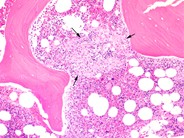

Bone marrow granuloma - 2.

Category: Reactive Marrow

The granulomatous lesion is shown at higher magnification to illustrate the cellular composition of macrophages with eosinophilic cytoplasm and scattered lymphocytes and plasma cells.